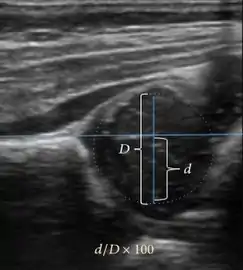

Ultrasound is the first-choice technique for diagnosis of newborns hip dysplasia. In experienced hands with appropriate technology, ultrasound can also be useful during the first year of life. Some European healthcare systems encourage universal ultrasound screening in neonates between the sixth and eighth weeks. Although it shows higher initial costs caused, it leads to significant reduction in the total number and overall costs of dysplastic hips undergoing operative and nonoperative treatment.[1]

Ultrasound allows categorizing pediatric hips, according to Graf’s criteria, in four main types: normal, immature, and dysplastic (subluxed and dislocated). This classification is based on measurements of the acetabular inclination angle (alpha), cartilage roof angle (beta), and infant age. The femoral head coverage can also be determined by dividing the length of the femoral head covered by the acetabular fossa and the diameter of the femoral head. Its lower normal limits are 47% for boys and 44% for girls (Figure 11).[1]

Figure 11:

Useful ultrasound measures in neonatal hip sonography, alpha and beta angles.[1]

Measurement of femoral head coverage.[1]

In a recent study, including newborns with high clinical suspicion for DDH (Ortolani/Barlow test, asymmetry in abduction of 20° or greater, breech presentation, leg-length discrepancy, and first-degree relative treated for DDH), hip sonography led to a change in clinical diagnosis in 52% of hips and to a change in management plan in 32% of hips. It obviated further follow-up in 23%, strengthening its role as an important technique reassuring the clinical diagnosis.[1]